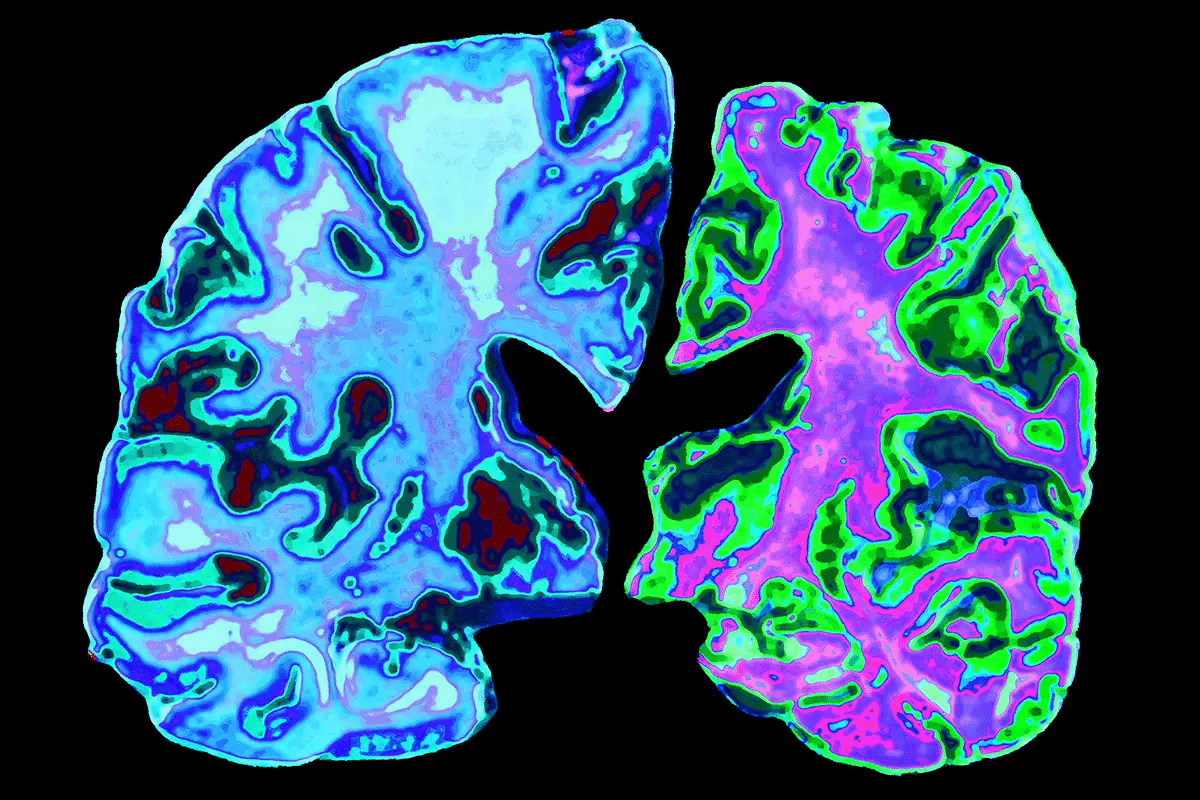

Cerebral Amyloid Angiopathy (CAA) is a condition where amyloid beta-peptide builds up in the brain’s blood vessels. This buildup can harm the brain’s blood vessels, affecting their function and structure.

CAA happens when amyloid beta-peptide gathers in the walls of brain blood vessels. This makes the vessels weak and more likely to burst, causing bleeding. The way amyloid beta-peptide interacts with blood vessel components leads to vascular problems.

The amyloid deposits in CAA are mainly amyloid beta-peptide, the same protein linked to Alzheimer’s disease. Yet, CAA is a unique condition that can happen alone or with Alzheimer’s disease.

Neuroimaging is key in diagnosing CAA. Magnetic Resonance Imaging (MRI) is very important. It shows signs like microbleeds and superficial siderosis.